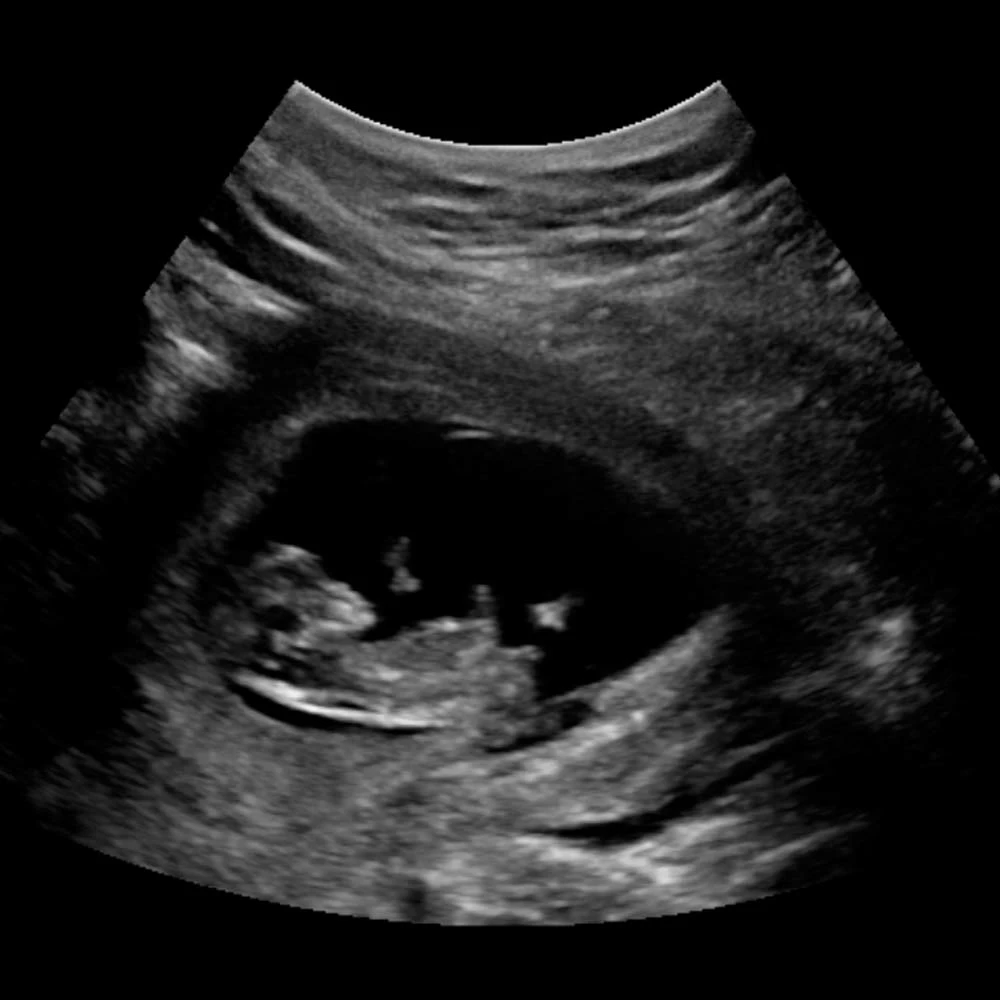

На четырнадцатой неделе при хорошем чувствительном аппарате УЗИ уже можно определить пол ребенка.